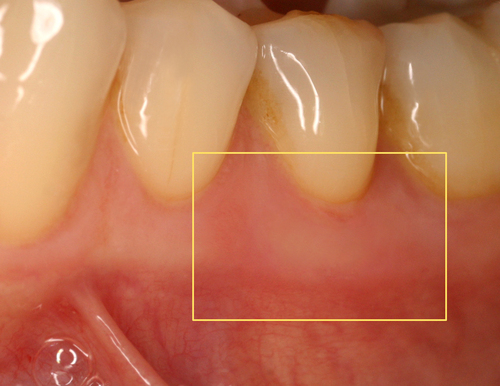

Cette biostimulation qui peut durer plusieurs minutes aboutit en général à une guérison très rapide et indolore des ulcérations gingivales (fig. 22)

Fig.22

Cicatrisation en quelques jours